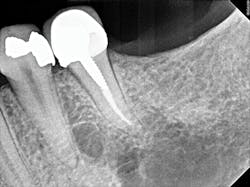

Figure 2: A periapical radiograph showing a suspicious area (i.e., radiolucency) approximating the apex of tooth No. 20, as well as the defective distal occlusal restoration on tooth No. 21